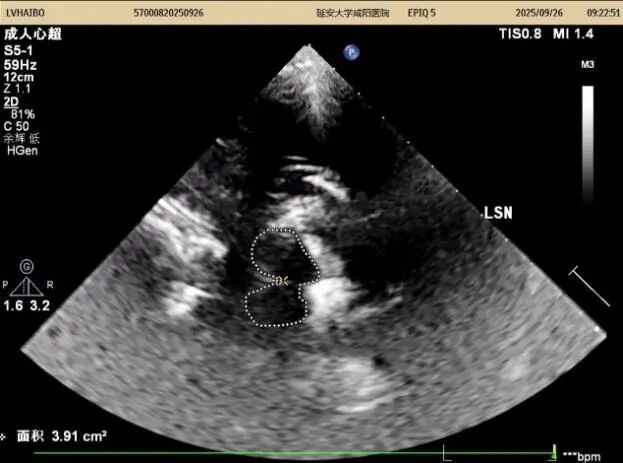

26日上午及下午14:00至15:50,以實際病例為媒介全流程質(zhì)控,從設(shè)備調(diào)試、探頭的選擇與放置、中腦(黑質(zhì)、紅核、導(dǎo)水管)、丘腦、第三腦室、豆?fàn)詈藚^(qū)域等的識別,到圖像優(yōu)化與測量規(guī)范,逐步演示標(biāo)準(zhǔn)操作流程,重點解析黑質(zhì)高回聲的識別與鑒別診斷。期間,結(jié)合患者病史,耐心答疑、細(xì)致指導(dǎo),引導(dǎo)醫(yī)師多維度理解技術(shù)要點,提升實戰(zhàn)能力。同時對我科前期工作給予高度評價。

在專題授課環(huán)節(jié),張教授以《帕金森病的TCS與神經(jīng)調(diào)控專家共識-解讀與臨床應(yīng)用》為題,從帕金森病的發(fā)病率及早期診斷難點切入,以問題為導(dǎo)向,結(jié)合國內(nèi)外研究,系統(tǒng)講解了中腦黑質(zhì)超聲的設(shè)備要求、檢查體位、標(biāo)準(zhǔn)切面及關(guān)鍵核團(tuán)評估要點,并通過典型圖像與病例,深入闡釋影像特征與臨床表現(xiàn)的關(guān)聯(lián)。針對實際工作中常見問題進(jìn)行了重點強(qiáng)調(diào),現(xiàn)場學(xué)術(shù)氣氛濃厚。王英莉主任總結(jié)指出,開展TCS需做到“準(zhǔn)、慢、細(xì)”—診斷精準(zhǔn)、隨訪耐心、觀察細(xì)致,并強(qiáng)調(diào)各亞專業(yè)組應(yīng)加強(qiáng)與臨床科室的縱深交流,融入科研思維。